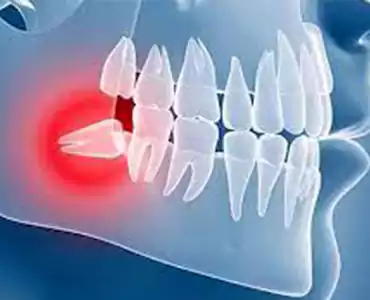

LATEST SERVICES

Our Services